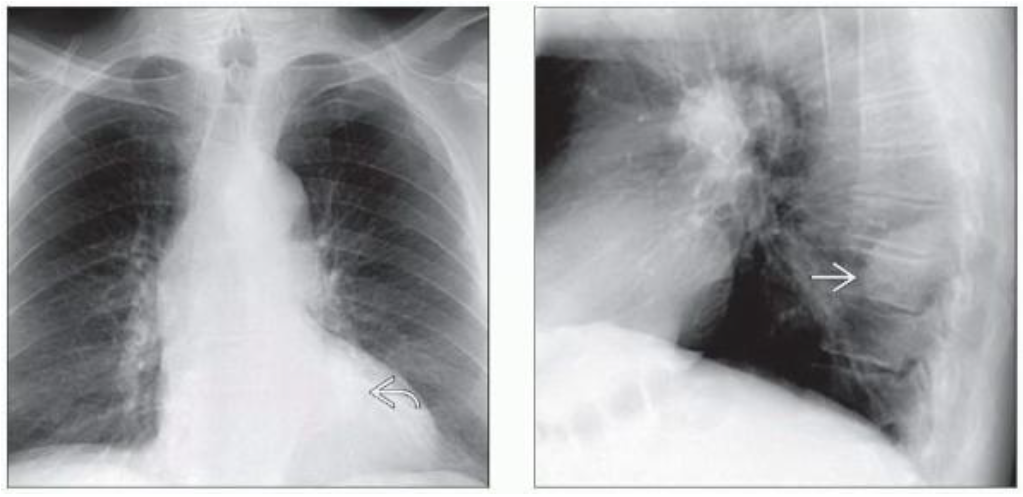

(左)56岁男性,患有1型神经纤维瘤病(NF1)。PA胸片显示双侧椎旁多发软组织肿块,外侧边界清晰,内侧边缘不可见。

(右)冠状FS-T2WI显示双侧多发高信号椎旁肿块,源自胸后神经根。丛状神经纤维瘤见于25%的NF1患者,难以治疗,4%发生恶变。

(左)82岁男性,无症状,椎旁神经鞘瘤。PA胸片显示左侧心后纵隔轮廓轻微异常。

(右)同一患者的侧位胸片显示肿块位于椎旁,由于位于肺外,可见不完整的肿瘤边界。该发现高度提示PNST,进一步MR评估可排除椎管内生长。